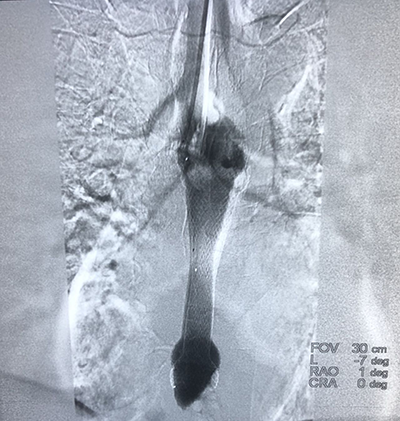

(腦腫瘤的介入治療)(子宮肌瘤的介入治療)

(脾功能亢進的介入治療)(食道支架植入術(shù))